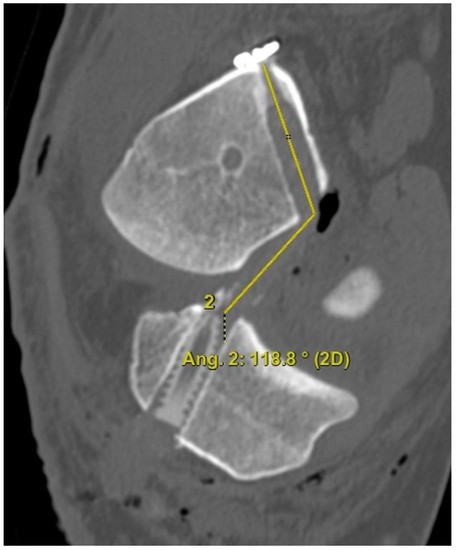

The 3D CT scans were imported into 3D software (AW Sever 3.2 PACS system, GE Healthcare; Chicago, IL, USA) for the assessments of the femoral graft bending angle and femoral tunnel length. The femoral graft bending angle was defined as the angle formed by the longitudinal axis of the femoral tunnel and the line connecting the intra-articular aperture of the tibial tunnel and the intra-articular aperture of the femoral tunnel (Figure 3). The femoral tunnel length was defined as the distance between the center of the extra-articular aperture of the femoral tunnel and the center of the intra-articular aperture of the femoral tunnel in a plane where the entire femoral tunnel could be viewed (Figure 4). Posterior wall breakage of the femoral tunnel was also checked.

Figure 3.

The femoral graft bending angle is defined as the angle formed by the longitudinal axis of the femoral tunnel and the line connecting the intra-articular aperture of the tibial tunnel and the intra-articular aperture of the femoral tunnel.